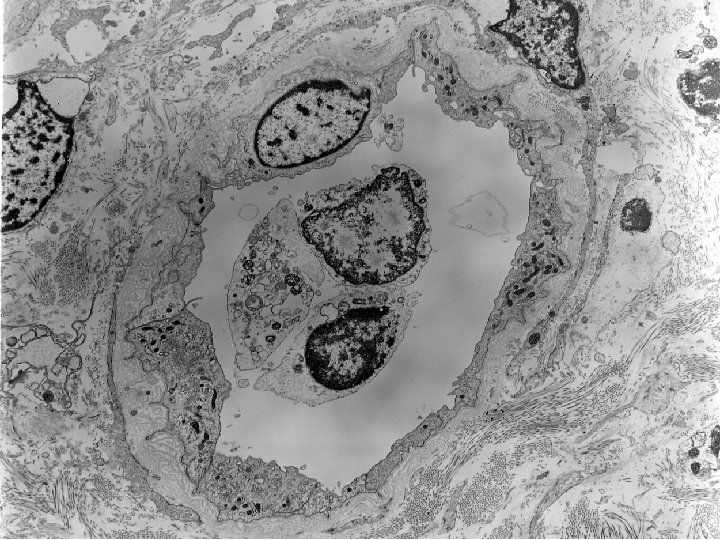

1996 Renal biopsy • Diagnosis: – Focal hyaline arteriolar change with probable consequent glomerulus

1996 Renal biopsy • Diagnosis: – Focal hyaline arteriolar change with probable consequent glomerulus sclerosis (1/7), possibly due to cyclosporine toxicity. – Focally marked fibrous intimal arterial thickening consistent with early chronic rejection. – g 0 cg 0 i 0 ci 1 t 0 ct 1 v 0 cv 2 ah 1